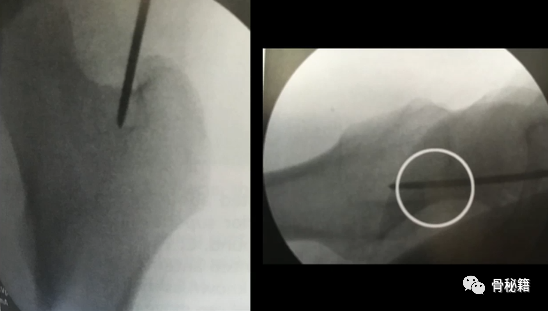

1、进钉点。髓内钉的位置在哪里最合适?

当然是髓腔的最中心,所以髓腔最中心的延长线就是最佳的进钉点。一般位于梨状窝。一个好的进针点可以保证力线,同时进钉后还有复位的作用,如果进钉点出现了偏移,可能整个手术都会有影响。好的开始象征着接下来手术的顺利,一定要取一个好的进针点。

他在正侧位的透视位置我们可以看到位于髓腔中心的延长线上

随着有外翻角的髓内钉的发明,我们现在目前用的可能多是大粗隆顶点进针的了

进针的角度,基本与股骨颈是垂直的角度

我们在做粗隆间骨折的时候由于骨折线经常经过进针点而出现近端内移的情况

注意采用快钻慢进,用套筒来纠正方向。